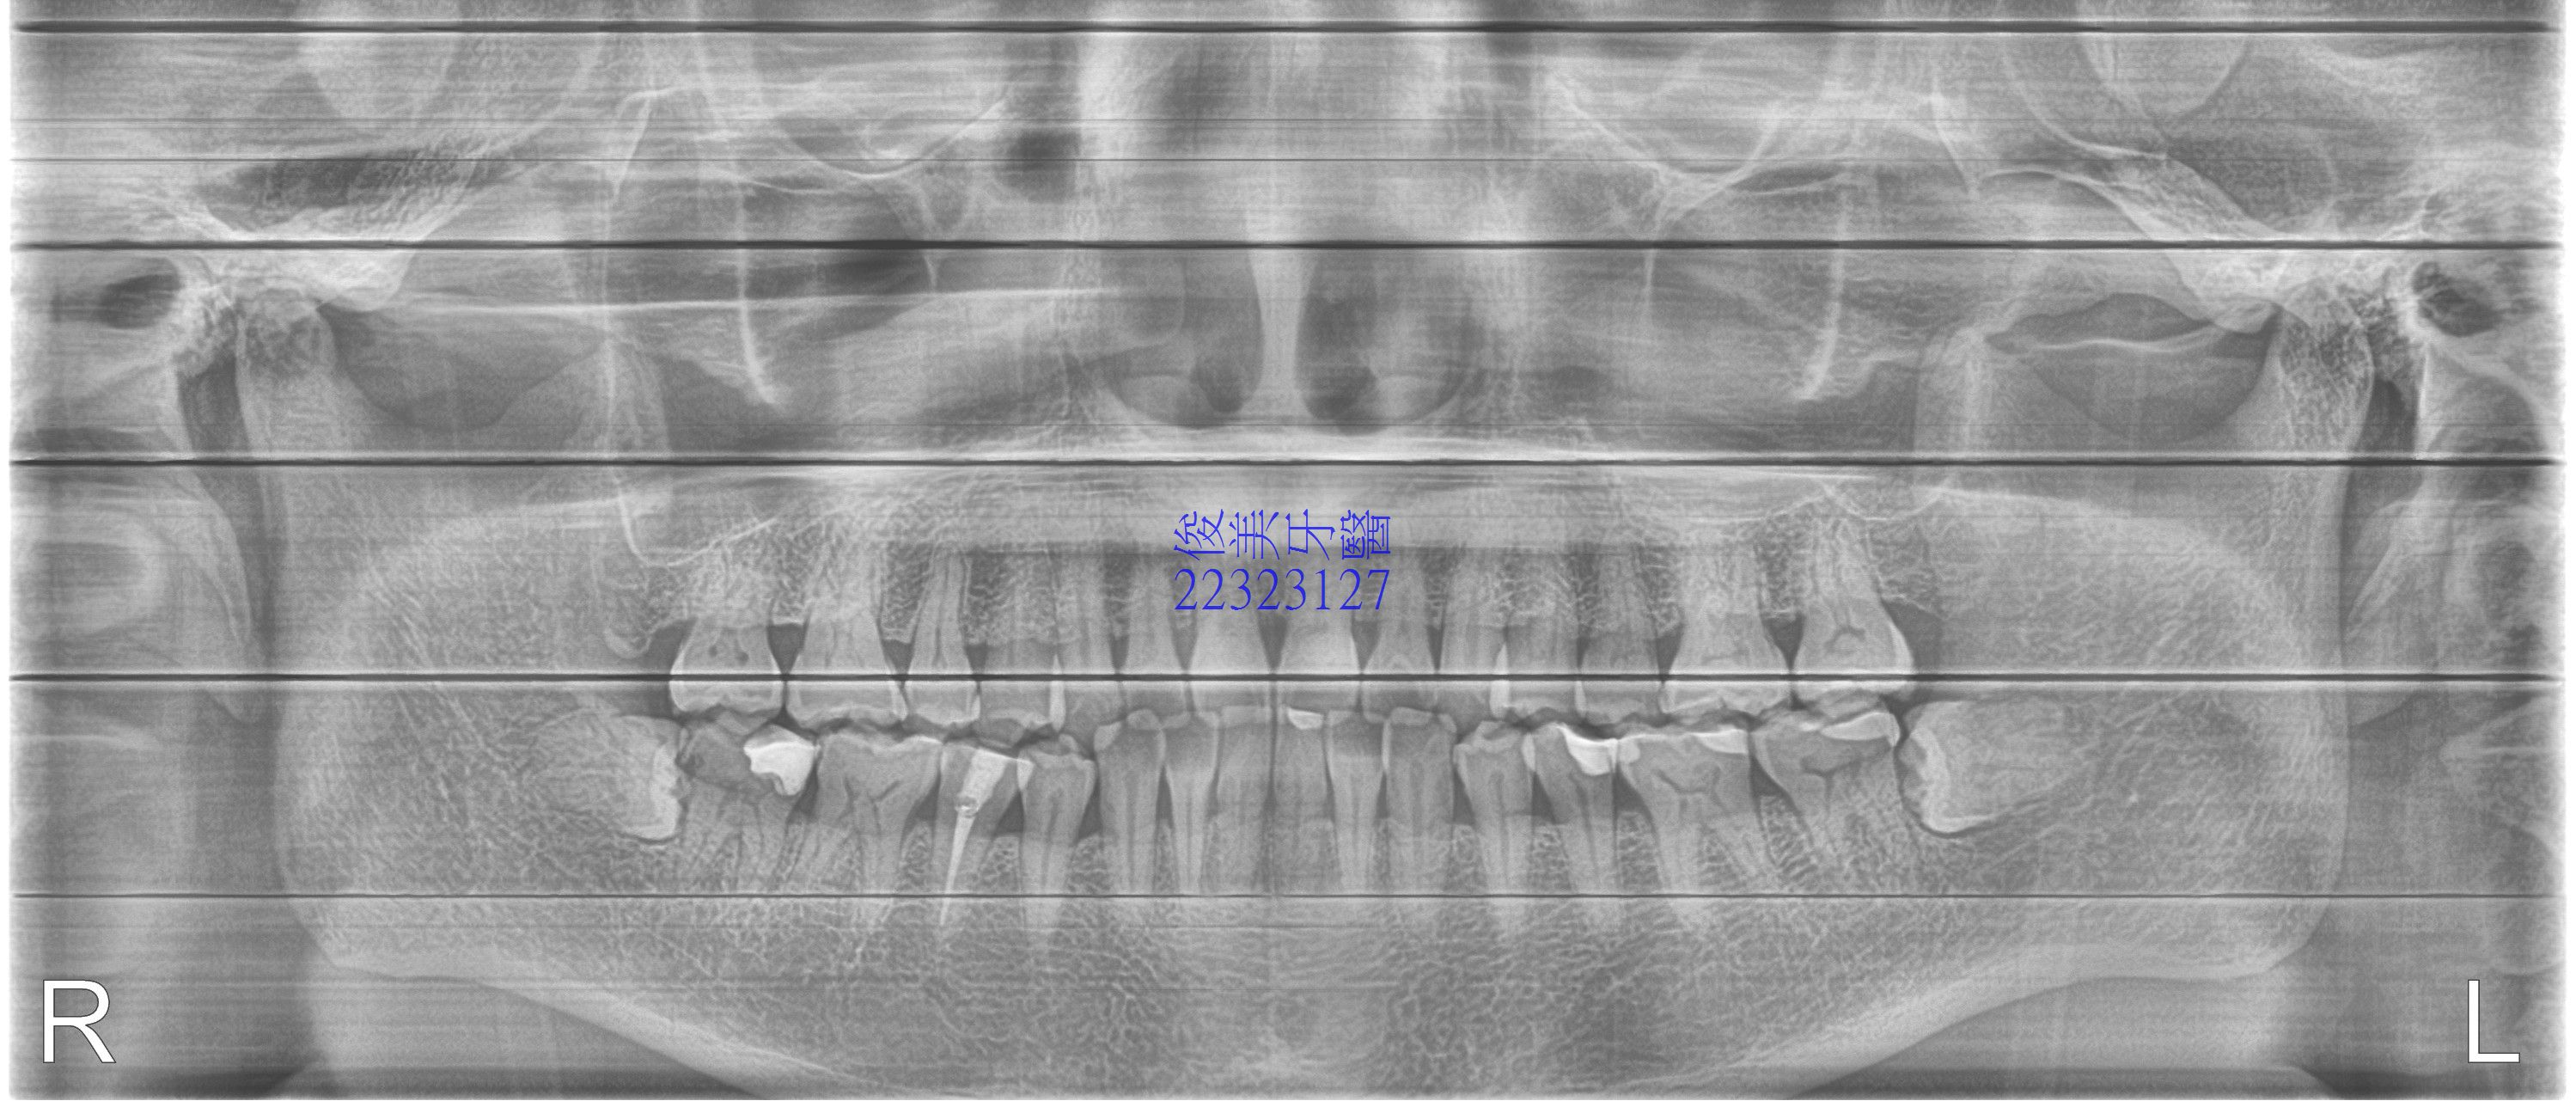

患者去年因左下智齒痛,而拔除了水平智齒,因年齡超過20歲已久,術後冰敷也未徹底,所以腫了一個星期,

但醫師有告知患者,右下也有水平智齒,一樣會塞東西,且前一顆牙已有蛀牙的現象,但患者自覺不痛,所以

沒有打算處理。

今年右下開始不舒服,腫腫脹脹的、前一顆牙齒也怪怪的,所以來拔右下水平智齒......